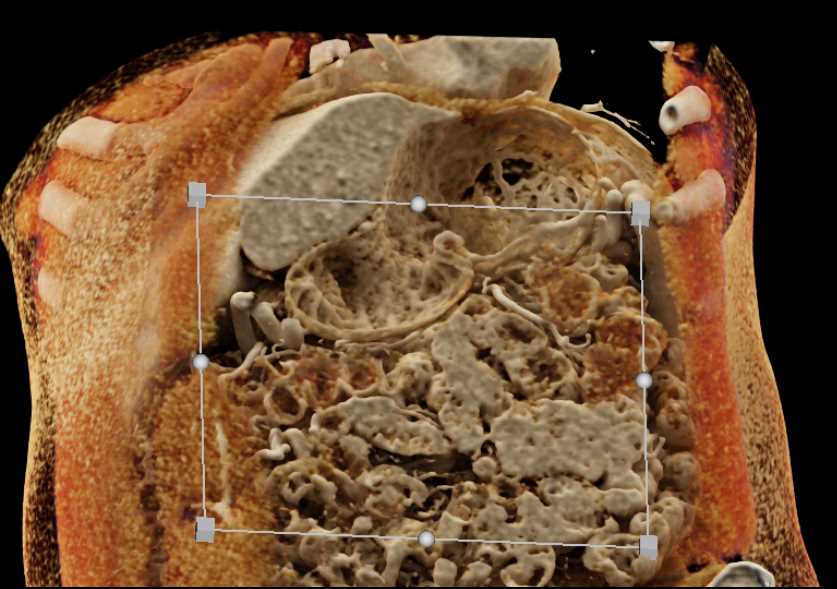

Neuroendocrine Tumor Pancreas